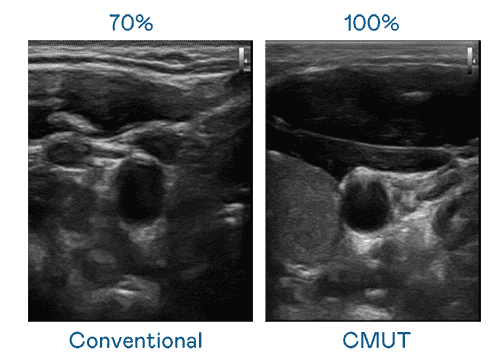

CMUT 技术是一种用电容式微机电元件来产生超音波讯号的技术。。。。与传统 PZT 压电式技术相比,,,CMUT 频宽增加 30%,,,更宽频的超音波讯号让影像解析度大幅提升,,,是实现高影像品质医疗超音波扫描、、、、促进精准医疗发展的关键技术。。。。

大频宽带来超清晰影像

超音波影像的解析度高低,,,,首先取决于探头能发出的讯号频宽。。。。尊龙z6 CMUT 可提供高清晰的超音波讯号,,提供高频宽、、高灵敏度、、影像纹理细节更高的超音波影像,,协助医护人员缩短影像判读时间及利用精准的医疗影像进行诊断。。。